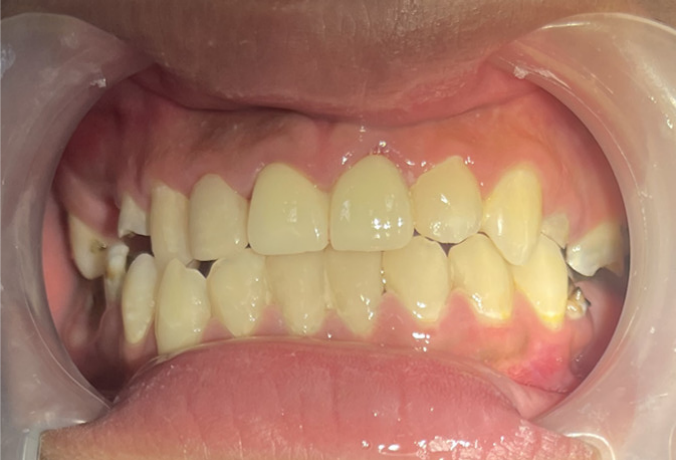

近日,广州市花都区人民医院口腔科通过规范的诊疗流程,为一名18岁男孩完成牙齿“蜕变”,让其重拾自信笑容。

这名男孩就诊时满口黑牙,颜值大打折扣。广州市花都区人民医院口腔科结合放射检查、内科治疗、外科干预及修复重建等诊疗环节,制定了“拍片检查—牙周治疗—拔牙—根管治疗—桩冠修复”的系统性方案,后续还将为其缺失牙进行种植修复。

从检查到修复,一口牙的“蜕变”离不开规范的诊疗流程与各环节的精准配合。广州市花都区人民医院口腔科团队将以专业、严谨的态度,为广大市民的口腔健康和美丽笑容保驾护航。